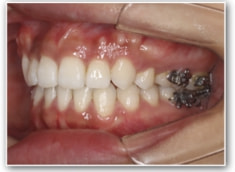

叢生+左下1番先天欠如ケース

治療法:裏側の矯正(リンガルブラケット:舌側矯正)

治療開始1年後